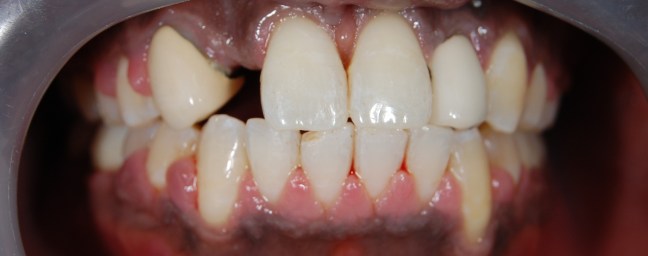

Kozmetikai és funkcionális kezelés: a kopott, elszuvasodott fogak szanálásával, hiányzó frontfogak híddal történő pótlásával, harapás megemelésével.

A választott korona típusa: CAD/CAM (komputer vezérelt tervezés/megmunkálás) technológiával készült cirkónium (fémmentes) szóló koronák, front híd.

A választott fogszín: BL 3 .

A protetikai munka elkészülésének ideje: 10 munkanap.